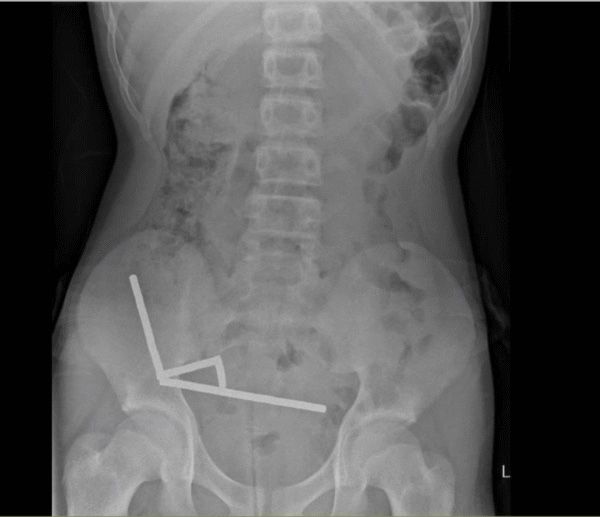

엑스레이 촬영 결과 의료진은 소년의 장 여러 부위에서 자석들이 사슬처럼 연결된 막대 4개를 확인했다. 복부 속에서 네오디뮴 자석들이 서로 강하게 달라붙어 막대 모양으로 뭉치면서 위험한 상황을 초래했다.

소년의 복부에서 막대 모양으로 뭉친 자석. 뉴질랜드 의학 저널 |